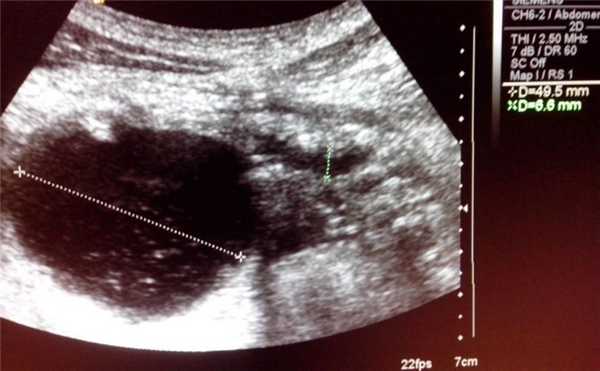

- Косое сканирование в эпигастральной области. Гипоэхогенное образование в хвосте поджелудочной железы (ПЖ)

- Косое сканирование в эпигастральной области. Гипоэхогенное образование в хвосте поджелудочной железы